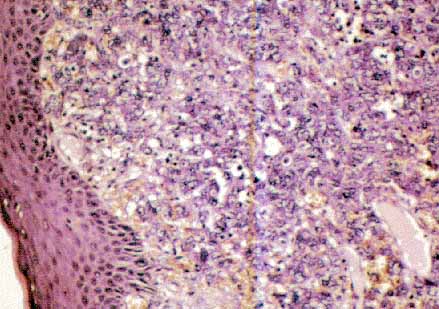

Fig 2: Dos crecimientos tumorales cutáneos enfrentados. La lesión más hipercelular corresponde al crecimiento sarcomatoso rabdoide ( H-E x 40).

fig. 3

Fig 3: Tumor rabdoide maligno de la piel. Se observa el dermis masivamente infiltrado por células tumorales (H-E x 200).